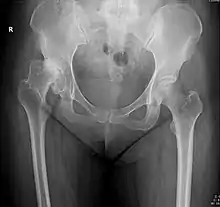

X-rays of hip dysplasia are one of the two main methods of medical imaging to diagnose hip dysplasia, the other one being medical ultrasonography.[1][2] Ultrasound imaging yields better results defining the anatomy until the cartilage is ossified. When the infant is around 3 months old a clear roentgenographic image can be achieved. Unfortunately the time the joint gives a good x-ray image is also the point at which nonsurgical treatment methods cease to give good results.